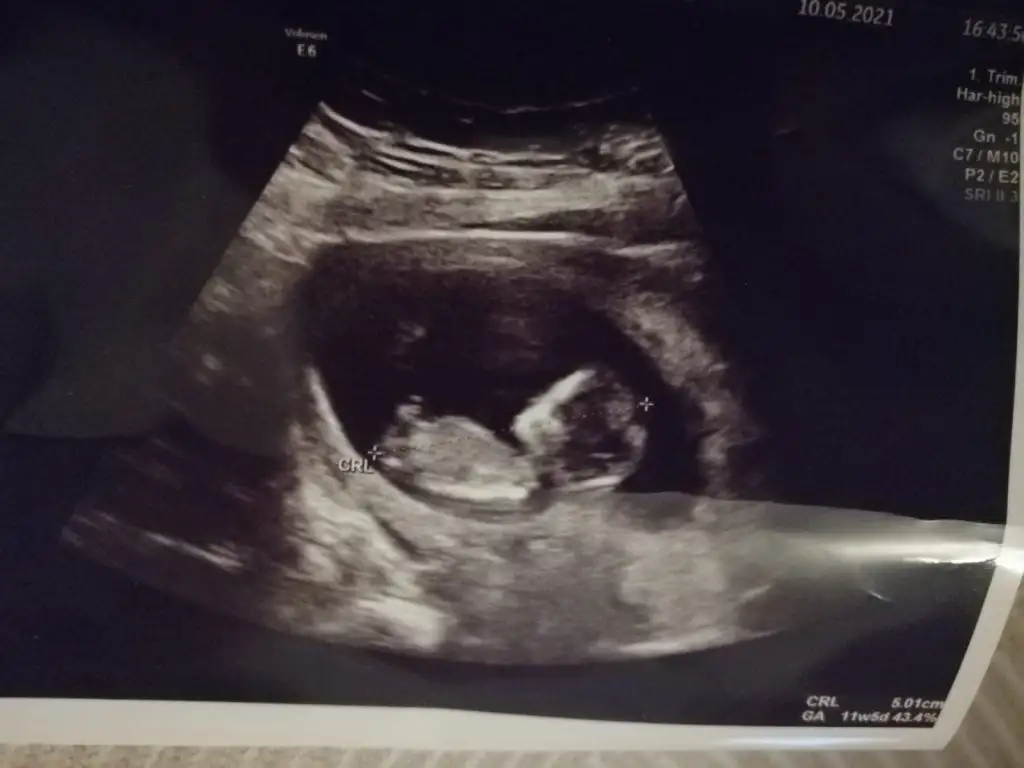

Ben de bakmanızı istesem 11+4 ultrason görüntüsü Ikra meyra

• IMG-20210510-WA0005.webp

19,4 KB · Görüntüleme: 79

• Screenshot_20210510-231802_WhatsApp.webp

11,5 KB · Görüntüleme: 86